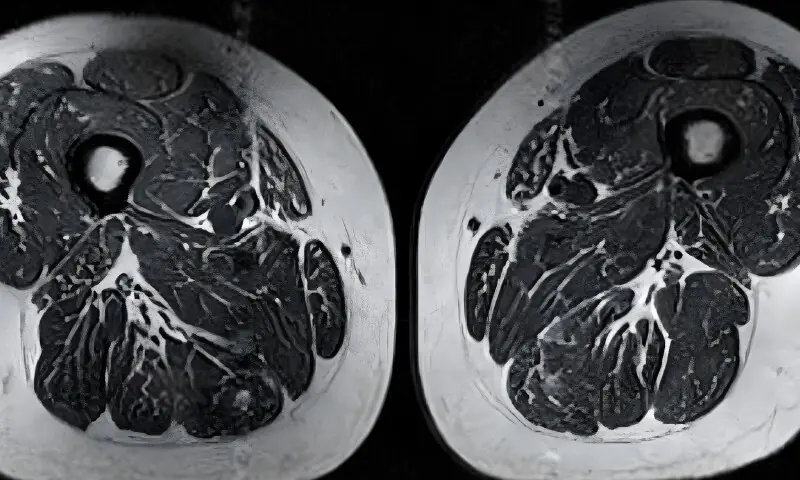

ایک طبی مطالعے میں ایک بزرگ خاتون کے ایم آر آئی اسکین کا حوالہ بھی دیا گیا، جس کی خوراک زیادہ تر میٹھے مشروبات، چاکلیٹ اور دیگر پروسیسڈ اشیاء پر مشتمل تھی۔ نتائج میں دیکھا گیا کہ ان کے پٹھوں میں چربی کی مقدار غیر معمولی حد تک بڑھ چکی تھی، جس سے ان کی جسمانی قوت متاثر ہوئی۔

ماہرین کا کہنا ہے کہ پٹھوں میں چربی کا یہ جمع ہونا صرف ایک مخصوص حصے تک محدود نہیں رہتا بلکہ پورے جسم کو متاثر کر سکتا ہے، جس کے نتیجے میں چلنے پھرنے کی صلاحیت کمزور ہونے اور مختلف دائمی بیماریوں کے خطرات میں اضافہ ہو سکتا ہے۔